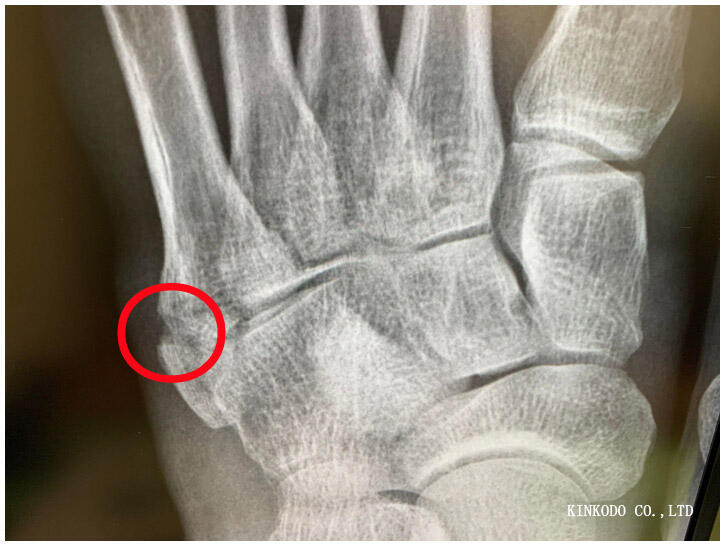

昨年は骨折。